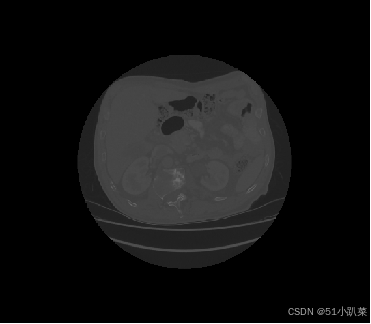

基于Unet分割医学2D3D图像

器官分割和三维重建